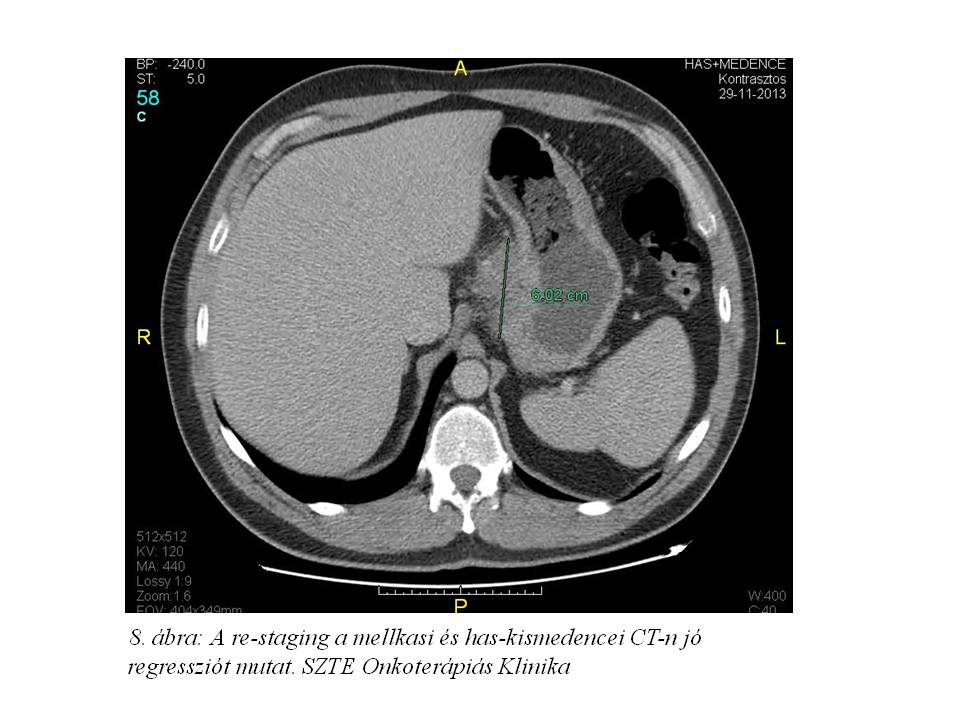

Első, perioperatív ECX kezelését 2013.10.03-tól kapta, mely előtt Gr.III-as anaemia miatt 6 egység vörösvértest transzfúzióban és per os vaspótlásban részesült. Kezelését filgrastim védelemben adtuk (inj. Zarzio 48 ME, 10 napon keresztül). A 3. ciklust követően bőrtünetei sokat javultak, de még kissé perzisztáltak. Re-staging mellkas, has-kismedence CT történt (2013.11.29. 8. ábra), melyen jó regressziót véleményeztek, azonban a lézió továbbra is 60 mm-es legnagyobb átmérőjű volt, és az artéria lienalistól nem tűnt elválaszthatónak. Emiatt sebészeti szakvélemény szerint műtét egyelőre nem volt javasolt, az onkológiai kezelés folytatását kérték.